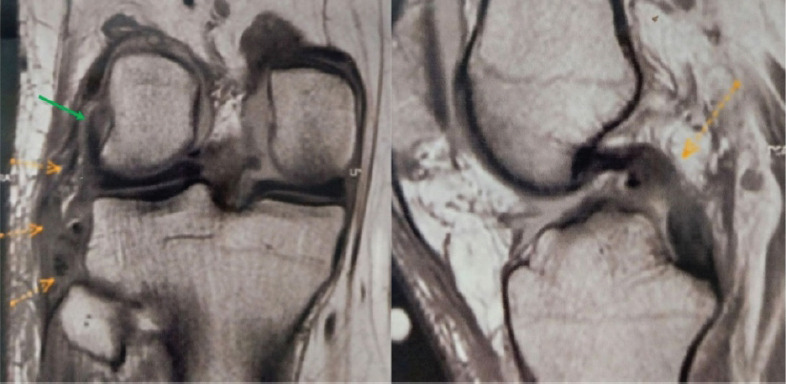

后外侧角(PLC)损伤通常与交叉韧带撕裂有关。历史上被称为膝盖的“阴暗面”,进步极大地提高了我们对PLC的理解,今天提供了各种管理选择。病例报告:我们提出的情况下,44岁的男性合并PLC和后十字韧带(PCL) 2级损伤。患者采用开放解剖arciero技术与胫骨前肌同种异体移植物进行孤立PLC重建。在随后的随访中,患者表现出良好的膝关节功能结果,无不稳定,易于进行常规活动,包括低至中等要求的体育活动。结论:PLC和PCL合并损伤的有效管理需要早期识别PLC损伤和具体病例的管理方法,考虑患者的病情、外科医生的专业知识和移植物的可用性等因素。同种异体移植物是自体移植物重建PLC的可行选择,与后者相比具有几个优点。

Case report: We present the case of a 44-year-old male with a combined PLC and posterior cruciate ligament (PCL) Grade 2 injury. He was managed with an isolated PLC reconstruction using an open anatomical Arciero-based technique with a tibialis anterior allograft. At subsequent follow-ups, the patient was shown to have excellent knee functional outcomes, no instability, and ease of performing regular activities, including low to moderate-demand sporting activities.